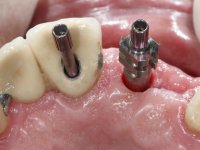

Segunda Fase

6 meses após a colocação da ponte, o paciente sofre um novo traumatismo comprometendo a viabilidade dos dentes 1.2 e 1.1. Foi realizada uma prótese removível acrílica para reabilitar provisoriamente o paciente enquanto foram extraídos os dentes 1.2 e 1.1 e foi colocado o implante no local do dente 1.1. Passados 3 meses foi realizada uma impressão ao implante colocado no 1.1 e simultaneamente foi feito um arrasto da ponte dos dentes 2.1 e 2.2. Para esse efeito no implante 2.1 foi utilizado um parafuso de uma peça de transferência. Dessa forma conseguiu-se impressionar corretamente a arquitetura gengival do sector antero-superior. O objetivo era simultaneamente impressionar corretamente esta zona e aproveitar a estrutura metálica desta ponte para confecionar a nova ponte de 4 elementos. Foi colocado um parafuso de cicatrização no implante 2.1 e foram acrescentados os dentes 2.1 e 2.2 na prótese removível. Com perícia laboratorial foi criada uma nova infraestrutura metálica de 4 elementos assente nos implantes 1.1 e 2.1 e com os elementos pônticos suspensos 1.2 e 2.2. No implante 2.1 manteve-se a conexão interna ao implante no implante 1.1 optou-se por uma peça intermédia facilitando a inserção da infraestrutura. A nova infraestrutura foi verificada em boca. Como pode ter havido alguma alteração da arquitetura gengival com a remoção da ponte e colocação do parafuso de cicatrização no 2.1, foi feita uma chave de silicone para permitir uma impressão de arrasto da infraestrutura metálica. Uma nova gengiva artificial foi realizada no modelo de trabalho de acordo com esta impressão de arrasto. Foi colocada cerâmica de tonalidade coronária e gengival. A peça protética foi aparafusada lentamente em boca para permitir uma adaptação dos tecidos moles. Após o correto assentamento e verificação imagiológica a ponte foi definitivamente apertada em boca e os orifícios de acesso obturados. Independentemente dos infortúnios que o paciente teve, pude ter a satisfação de o ver contente com esta reabilitação.